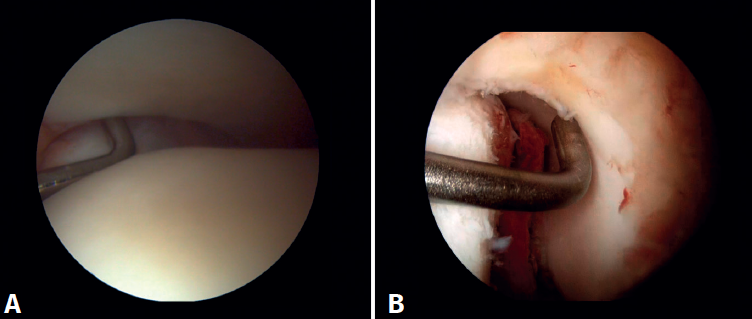

Surgical technique: arthroscopic treatment of acute medial complex injuries

In terms of surgical technique, the working portals are established in the same way as in conventional ankle arthroscopy: one anteromedial portal and one anterolateral portal. We always start with diagnostic arthroscopy to confirm the injury to the deltoid ligament. A probe can be used to verify the laxity of the fibers, and a test can be performed by inserting the probe through the medial groove: the lesion is confirmed if the instrument passes through. For repair, the viewing portal will be the anterolateral portal, thus allowing us to work more directly through the anteromedial portal. The anterior fibers of the superficial tibiotalar and intermediate fibers of the deep portion of the deltoid ligament are the ones that can be repaired with the arthroscopic technique(38). Once the ligament has been identified and dissected, a suture is passed between the fibers using a suture passer. The medial malleolus anchorage zone is prepared with a shaver or a small burr. With the ankle in neutral position, the anchor is inserted while maintaining the tension of the sutures. The intersection of the line parallel to the tibiotalar joint and a perpendicular line marked from the tip of the malleolus and along the lateral border of the malleolus can be used as an anatomical reference for placement(21). After reduction, we again test the fibers for tension and passage of the probe through the medial groove, to confirm adequate repair (Figure 8).